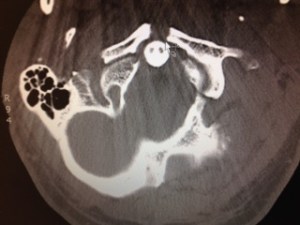

Phew!!! Happy Wednesday…it’s been one long week!!!…and it’s only the middle of the week! My wonderful hubby broke his neck and so I’m learning all sorts of NEW things about vertebras, braces, etc…but we are extremely blessed to have him still with us!

I am so sorry! Your attitude is an inspiration – instead of asking “Why me?” you are already focusing on gratitude and working through the situation. Sounds as if your husband is in good hands medically -speaking – and that can be a huge relief. The body has an amazing ability to heal and I will pray for a full recovery for your husband. An x-ray is the perfect picture for today’s post.